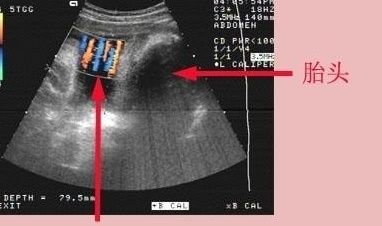

【 怀孕36周脐带绕颈3圈,羊水又偏少,该怎么办?】脐带绕颈三周和羊水偏少都是孕晚期要引起重视的现象,怎么都让这位准妈妈给碰上了。

一般来说,脐带绕颈三周占总分娩数的0.5%左右,题主现在孕36周,离预产期还有一个月时间,胎儿可能会绕出来的或者转变为脐带绕颈1-2周。

脐带绕颈这个现象是没办法干预的,只能靠宝宝自己努力,宝宝要是觉得不舒服的话,他会自己调整的,只要宝宝的胎动和胎心率正常,准妈妈是不需要特别紧张。

脐带绕颈现象虽然是很常见的,但遇到羊水偏少的情况下,也是有可能造成胎儿缺氧和宫内窘迫的。准妈妈要多喝豆浆,多喝温开水,平常要多喝汤。

因此,准妈妈要记得按时去产检,适当的时候医生会让吸氧,同时注意每天数胎动,发现胎动减少或者胎动过于频繁,都要及时就医。